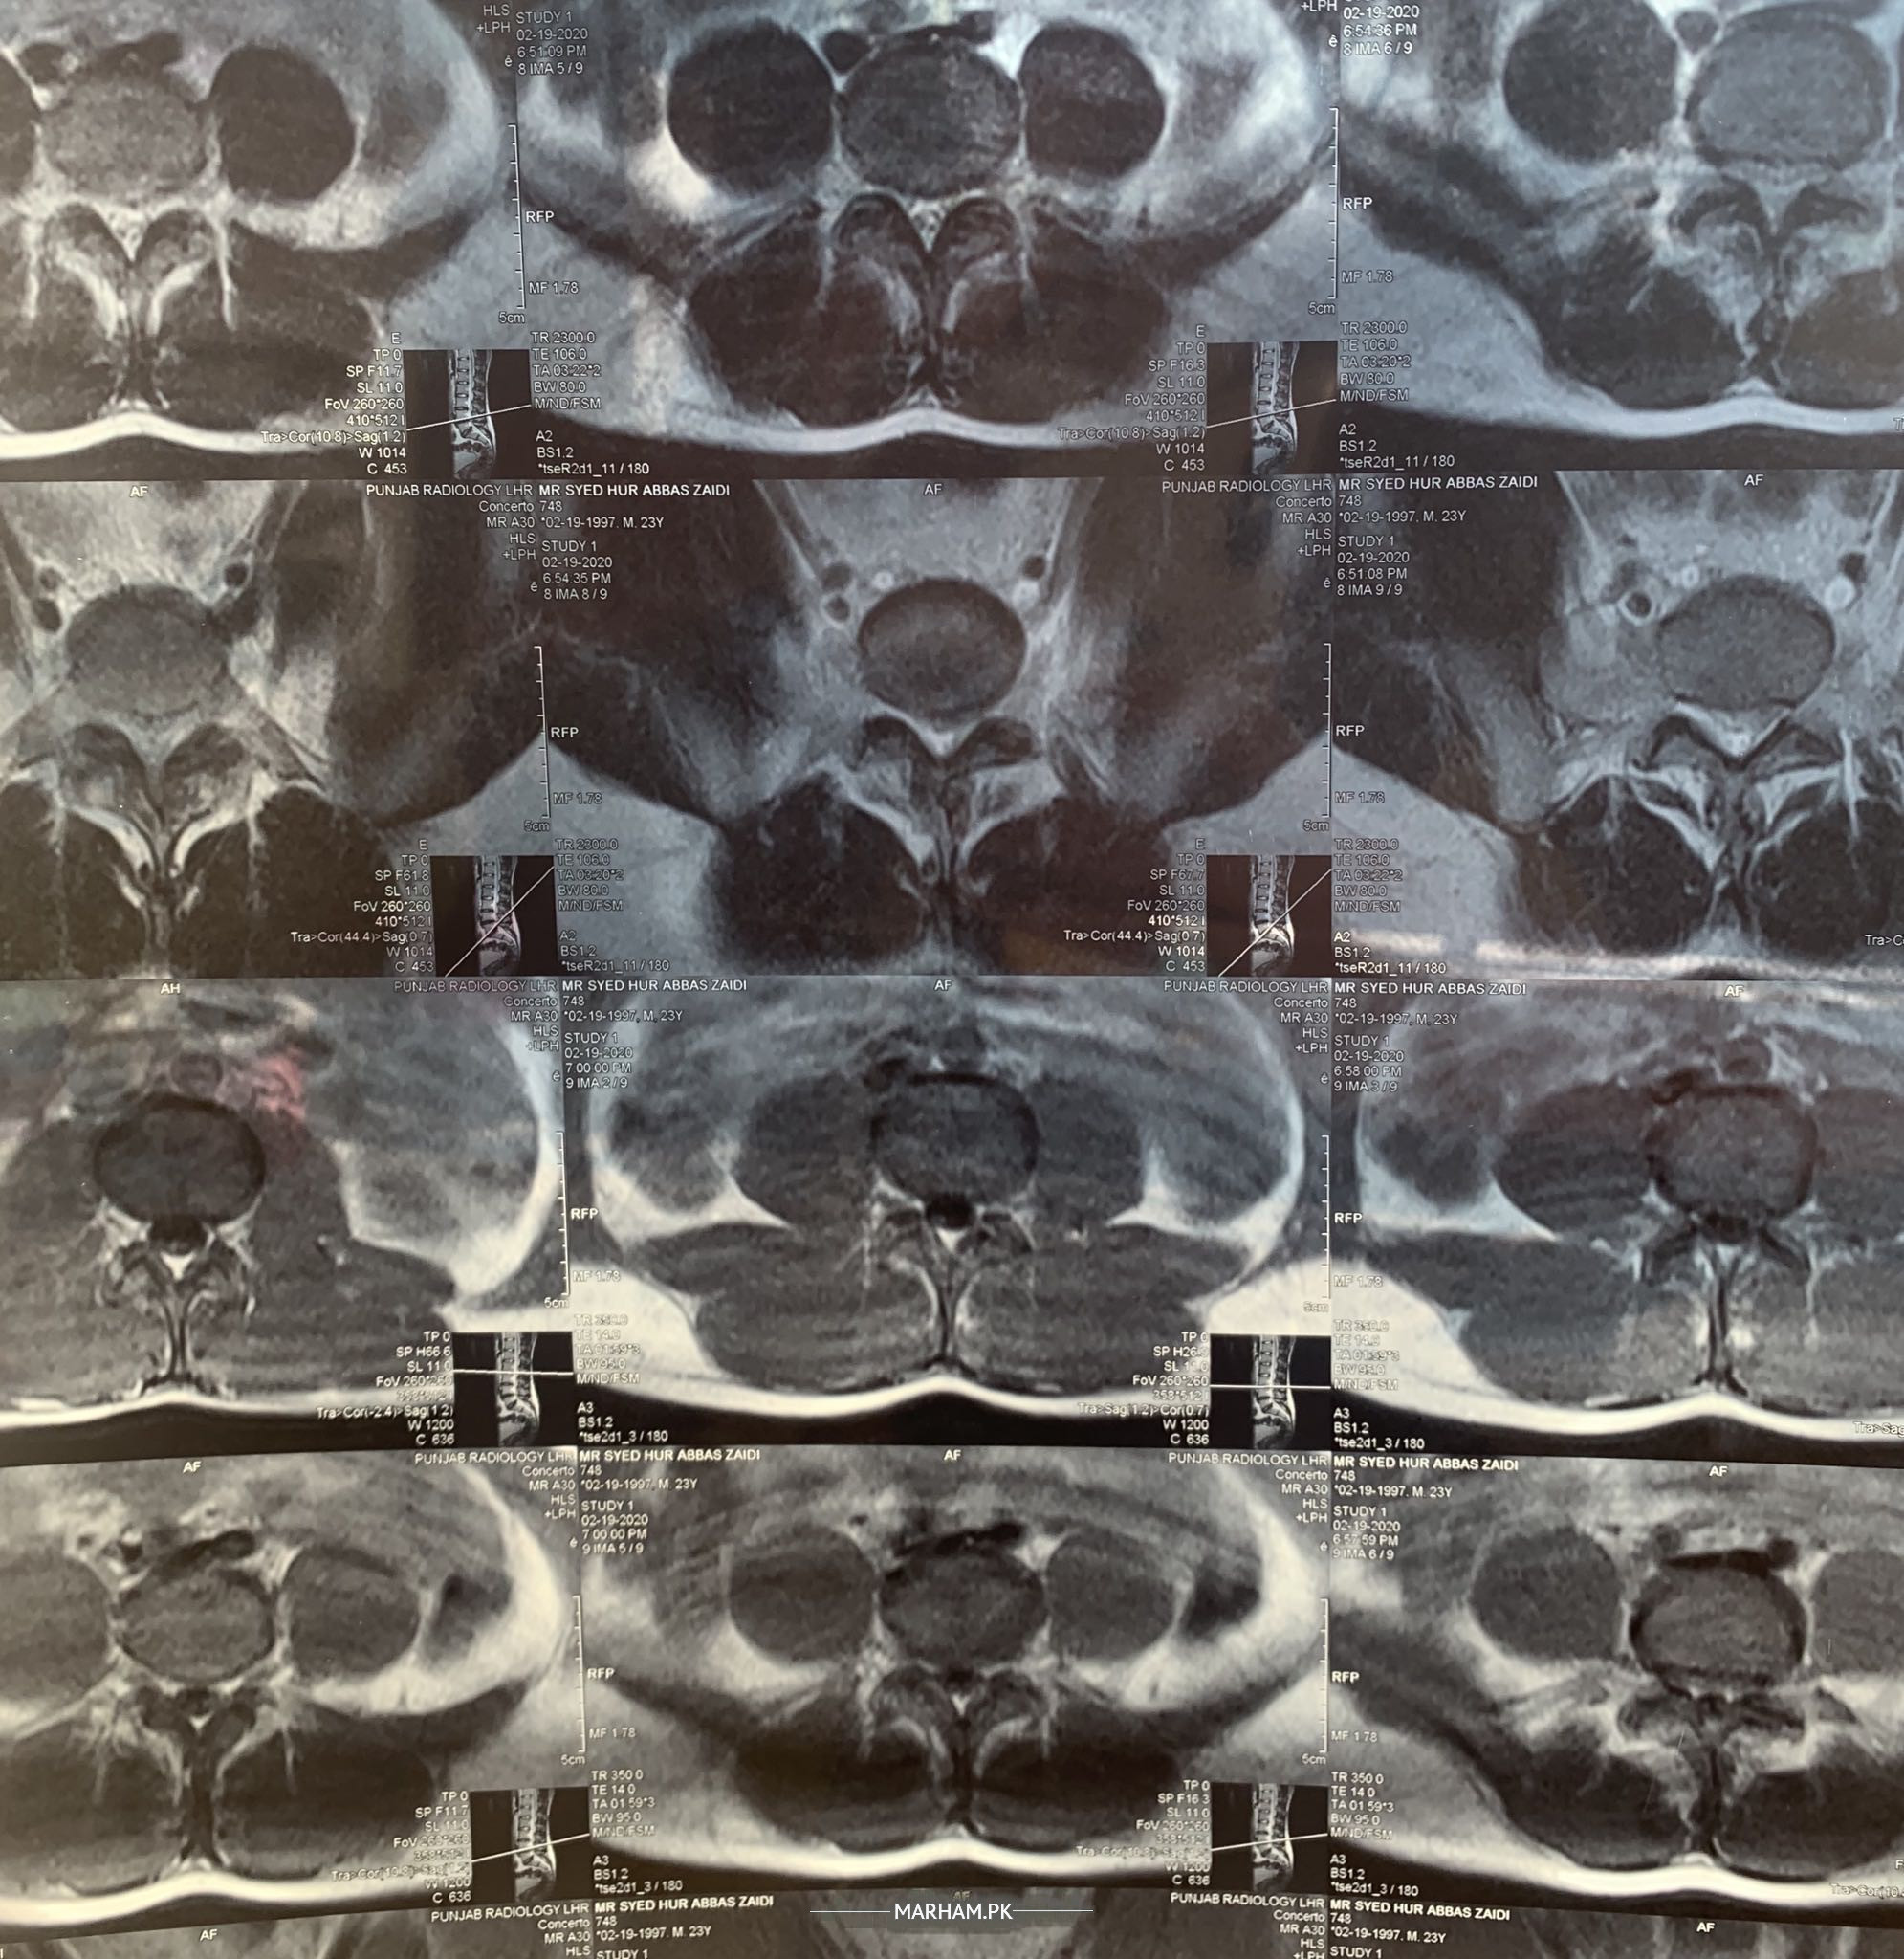

Actually when i was free after finishing my 10th grade I started gym and while doing gym i got a little bit lower back issue from there,but I ignored and back to normal but time to time that pain becomes so hard i even also don’t care to much about it and feel relax,i also did a heavy weight lifting job loading and unloading trucks but now im in a serious condition i cant endure that pain. I visited neurosurgeon physiotherapist aswell but still im not out of my pain im attaching my MRI REPORT in file kindly tell me any solution for it really appreciate thanks

Yeah i share all my MRI films and XRAY aswell please have a look on it thanks

MRI

There are disc bulges at multiple level. At this age we first try physiotheraphy and pain medication. But u have weakness in lower limbs or any loss of sensation or loss of control of Bowl or bladder then surgery. Physical examination is necessary for best opinion.

Xray

your l5-s1 is messed up with l5 rotation and severe hypolordosis. physical therapy or meds will not help, not even in 100 years. we treat this everyday as we do in USA. let us know if you want our treatment